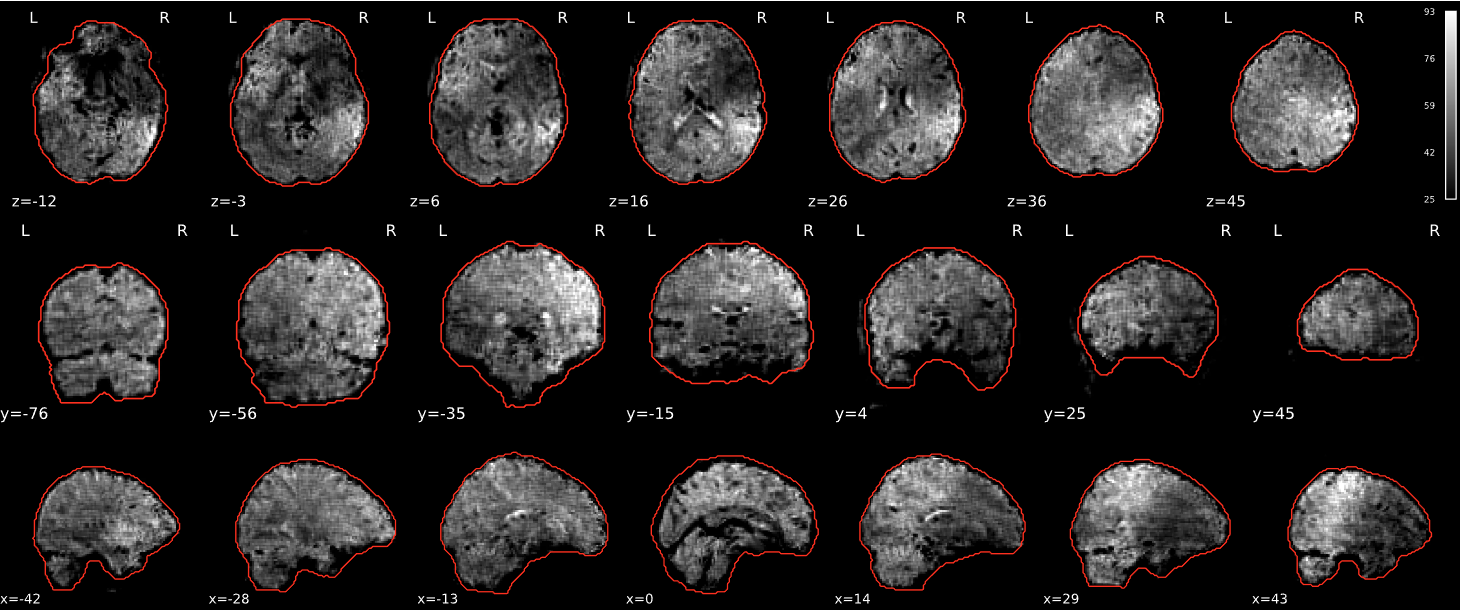

EPI tSNR

In the signal to noise ratio images of the resting state image the desired signal is compared to the amount of background noise. It is important to check all the views (sagittal, coronal, axial) because some artefacts (e.g., stripes) may be evident only in one particular view.

Example of a good subject

- Signal to noise is symmetrically distributed and there is no signal distortion

Example of a bad subject

- Asymmetry

- Potential signal distortion (might represent an artefact)

- Signal drop-out

- Stripes artefact

Clear large artefact (e.g., zebra stripes in example 1) are worth the exclusion of the subject. If you are unsure, check the other quality metrics for that subject to decide whether they should be excluded.

Summary

| good | bad |

|---|---|

| Symmetrical distribution of noise and signal | Asymmetry |

| No disruptions of the signal (no “black patches”) |

Potential signal disruptions (could be related to artefacts) |

| No stripes (sign of high motion) |

Signal drop |

| Stripe artefacts (“zebra” stripes due to motion) |